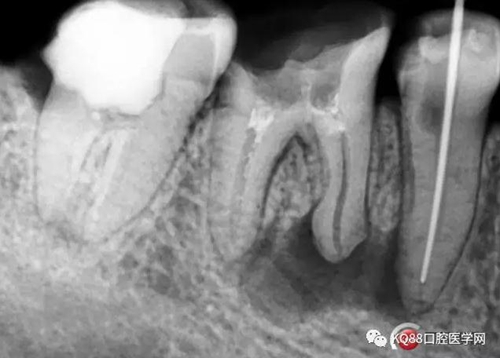

處理與結(jié)果:45局麻去髓,在確定工作長(zhǎng)度時(shí)拍X線片顯示:46近中根尖周稀疏影,且邊緣呈淡薄云霧狀。

例2 45根管測(cè)量時(shí)X線片所見